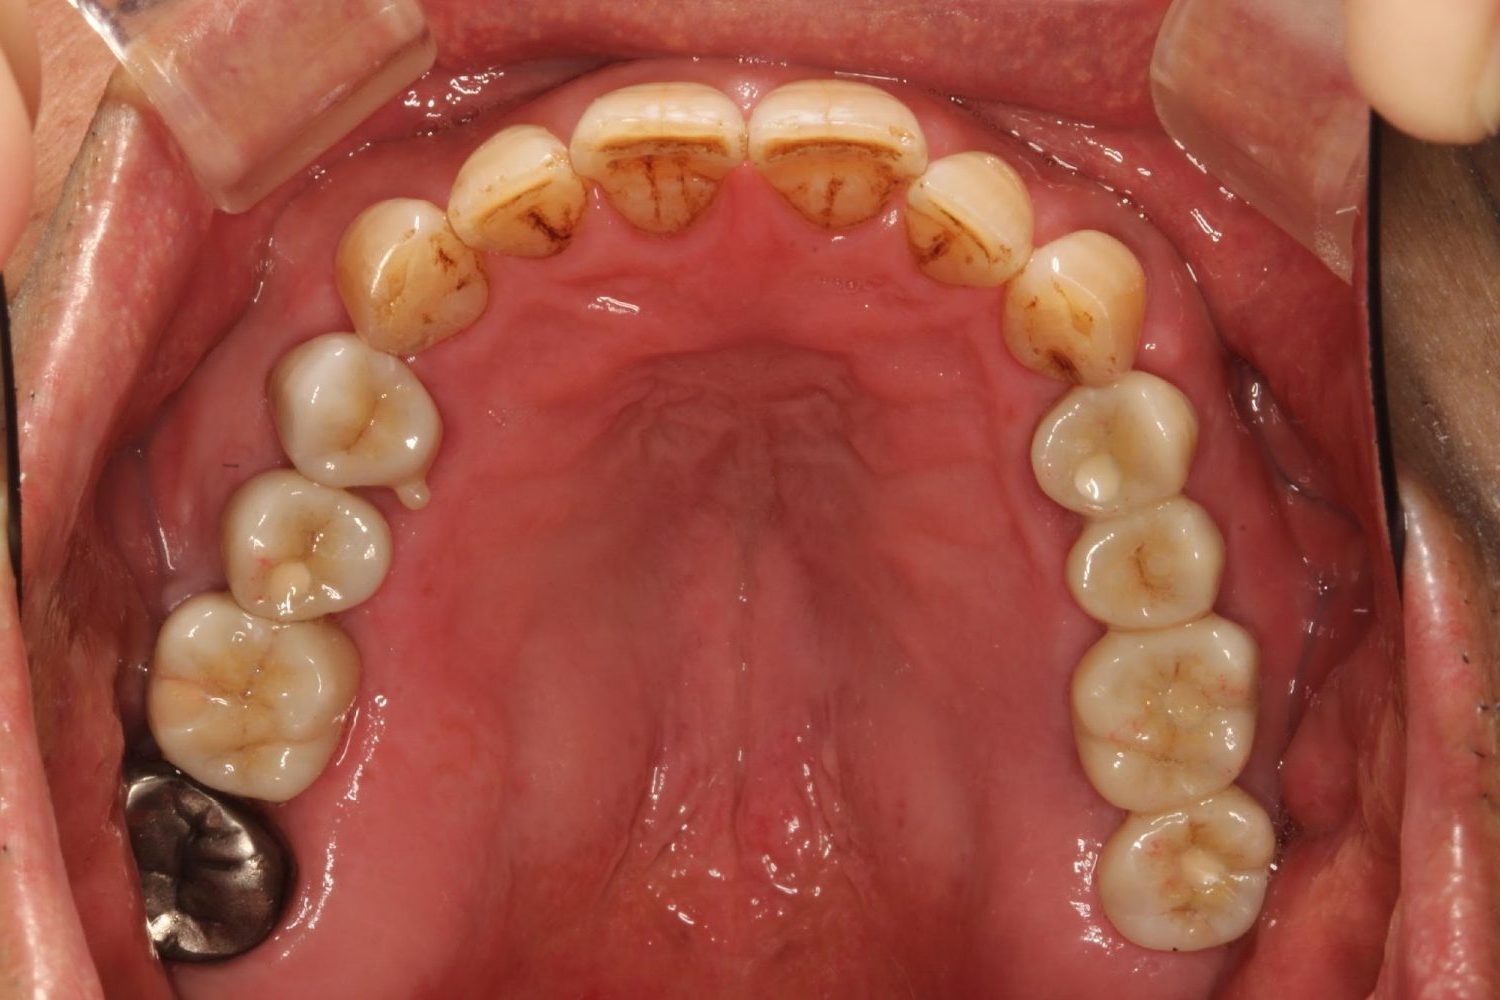

インプラント治療の症例紹介③

Before

After

主訴

むし歯の治療

治療内容

保存不可能な歯の抜歯

下顎にインプラント埋入し咬合再構成

治療費

2,688,400円(税込)

治療期間

14か月

治療回数

21回

想定されたリスク

※上部構造の形態が複雑になるため清掃が難しくなる。インプラント周囲炎の恐れがありました。

多数歯う蝕および多数歯欠損による咬合崩壊、保存不可能な歯の抜歯により上下無歯顎に。下顎に6本インプラント埋入する事で咬合再構成を行った。